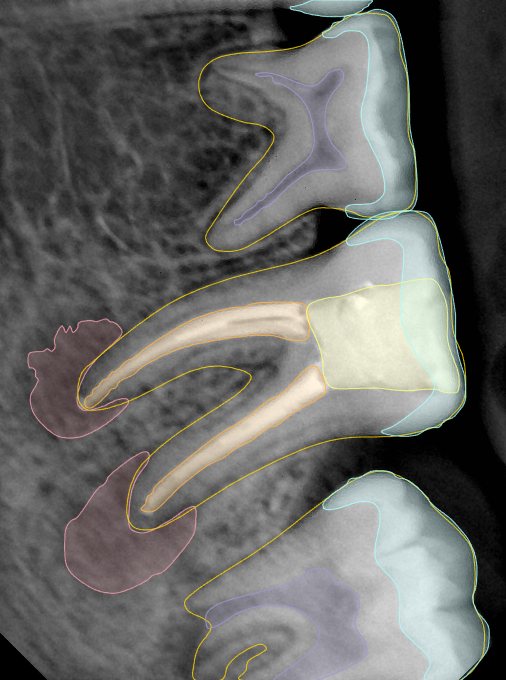

第二版算法问题测试

Updated: 2026-04-13(更新日期)

| 第一版 | 第二版 | 是否解决 | |

|---|---|---|---|

![]() | ![]() ![]() 边角识别有问题 龋齿识别不全 牙髓识别不全 | ![]() | 解决 |

![]() | ![]() 边角识别有问题 识别信息有误 自查(牙冠识别不全) | ![]() | 解决 |

![]() | ![]() ![]() 边角识别有误 大范围填充识别遗漏 | ![]() | 解决 |

![]() | ![]() 识别信息不全 | ![]() | 解决 |

![]() | ![]() ![]() 边角问题 牙胶识别不全 牙冠识别不全 | ![]() | 解决 |

![]() 换图片 | ![]() | ![]() 牙冠部分稍微白了一些就识别成小范围修补,部分判断异常 | 部分解决,修复类略敏感,牙冠部分稍微白了一些就识别成小范围修补,部分判断异常。 |

![]() | ![]() ![]() 牙冠识别不全 牙髓不全 根尖炎龋齿识别有误 | ![]() | 解决 |

![]() | ![]() | ![]() | 解决 |

![]() 换图片 | ![]() | ![]() | 解决 |

![]() | ![]() 牙冠识别有误 | ![]() | 解决 |

![]() 换图片 | ![]() ![]() 边角识别有误 | ![]() 修复类敏感 | 部分解决,图像过白,导致修复类判断异常。 |

![]() 换图片 | ![]() 牙冠识别不全 | ![]() 修复类敏感 | 部分解决,图像过白,导致修复类判断异常 |

结论:修复类出现了不鲁棒的情况,后续需要加入轮廓的扩充数据进行增强。